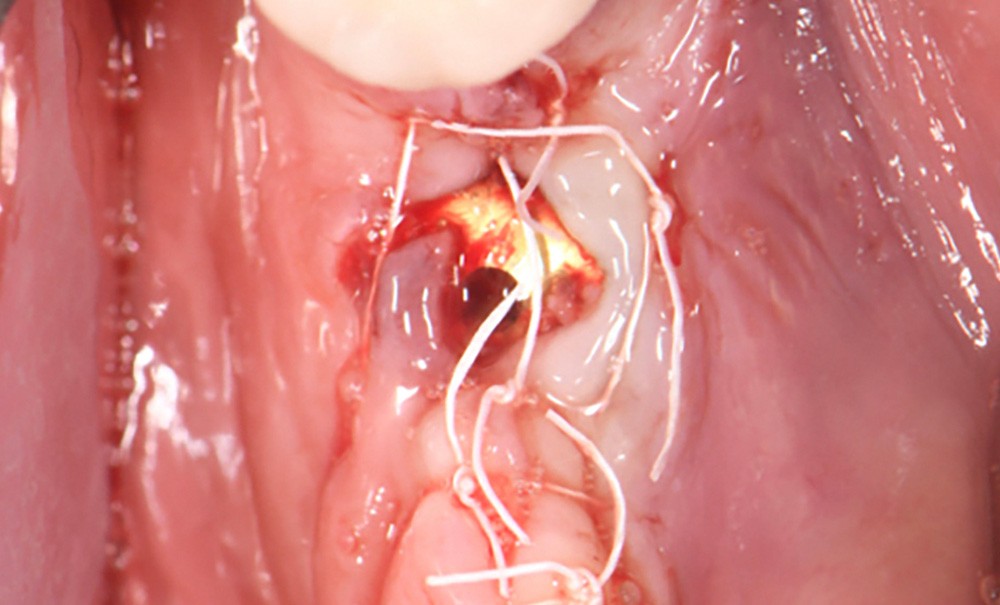

Actes préopératoires

La couronne a été déposée et une vis de couverture mise en place. La patiente a reçu un nettoyage supra-gingival général avec une attention particulière pour l’implant 47, et une irrigation locale avec du gel de chlorhexidine et du peroxyde d’hydrogène pour réduire l’inflammation des tissus. De l’amoxicilline (3 x 500 mg) a été prescrite, à commencer la veille de l’intervention chirurgicale.

En ce qui concerne le traitement de la péri-implantite, l’identification et le contrôle des facteurs de risque locaux et systémiques, ainsi que la qualité des tissus mous environnants, sont des facteurs à prendre en compte. En ce qui concerne la partie prothétique, une évaluation minutieuse de la prothèse doit être faite pour envisager si nécessaire une nouvelle conception. L’approche électrolytique exige que la prothèse sur l’implant…